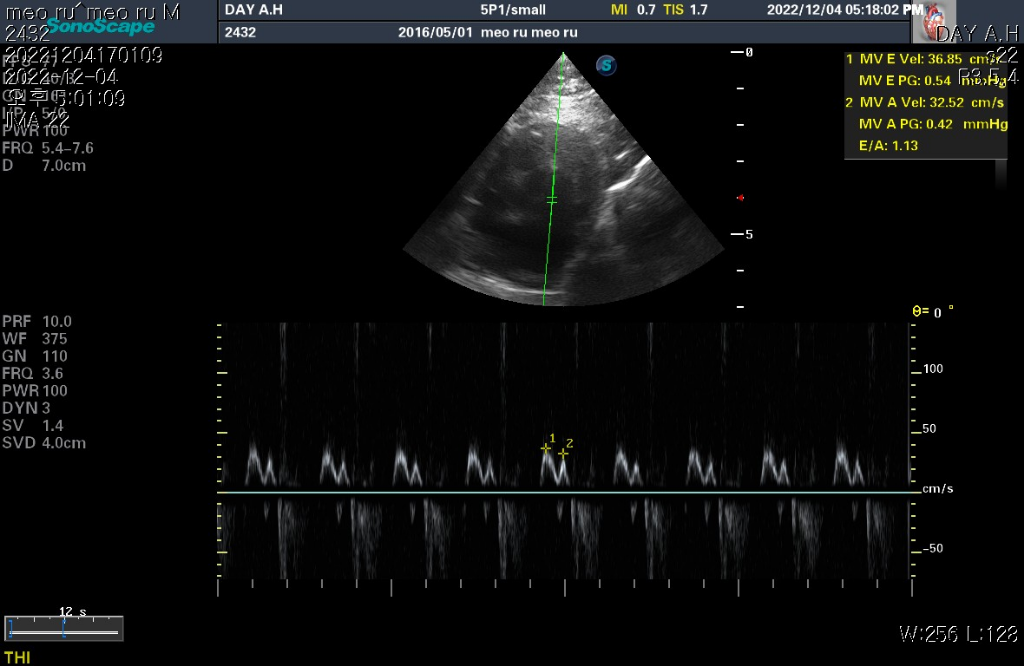

하지만 심장 질환의 잠정적 확진 golden standard는 심장 초음파 검사로 심장 초음파 검사상 심장의 벽 구조가 6mm이상이라면 HCM의 가능성이 매우 높다고 판단합니다.

현재 첨부한 사진상에서 6mm이상의 직경을 보이는 사진들이 존재하기 때문에 해당 검사를 진행한 수의사의 기준상 HCM의 가능성이 높다고 판단하는것은 합리적입니다.